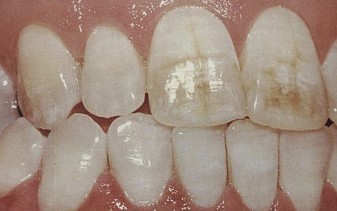

ingestion of excess amount of fluoride, retention of amelogenin protein in enamel, hypomineralization creating chalky white areas, must be bilateral symmetrical distribution with previous exposure to Fl

fluorosis, mottled enamel

from use during tooth development; may also discolor skin, sclera, thyroid; RX for acne, cystic fibrosis, RA

tetracycline staining